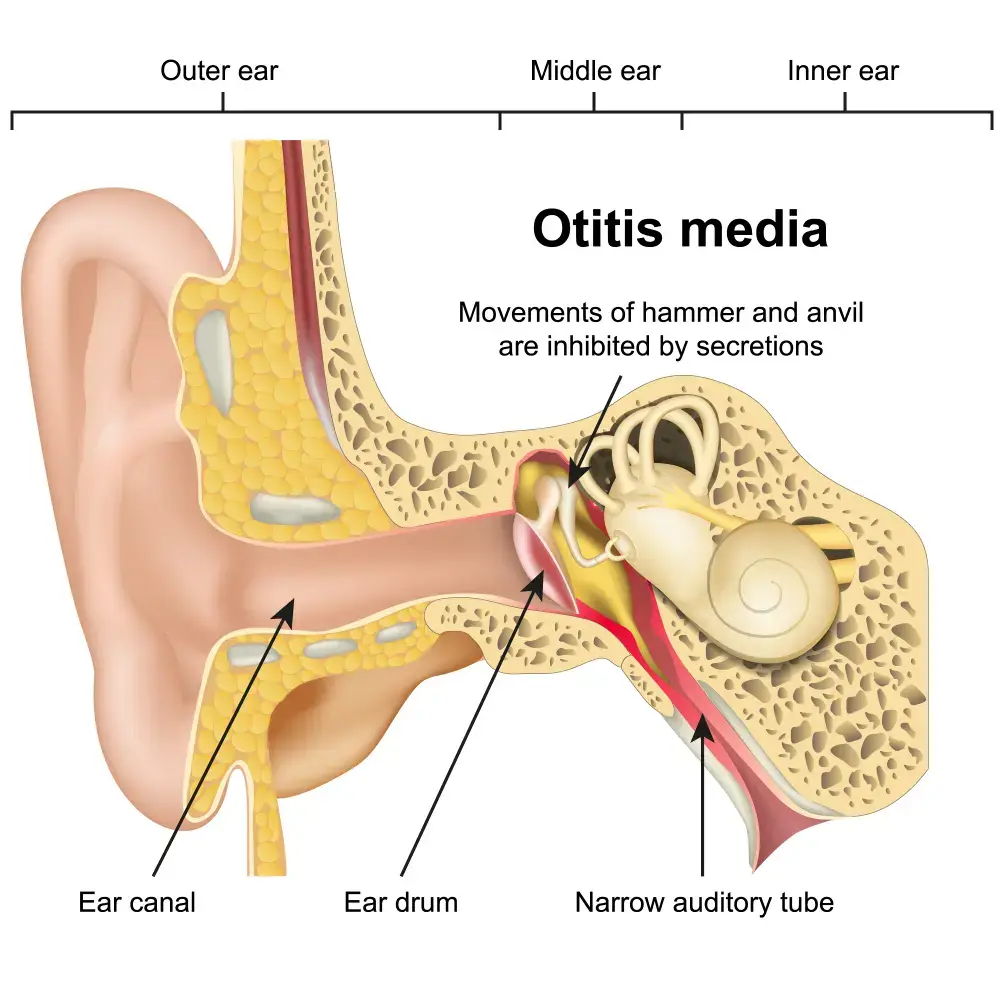

- Ear Infections • Georgetown • osteopathy • Natural Health Clinic of Halton (March 26, 2022)

- Pediatric Otitis Media (OM) • Georgetown • osteopathy • Natural Health Clinic of Halton (March 31, 2022)